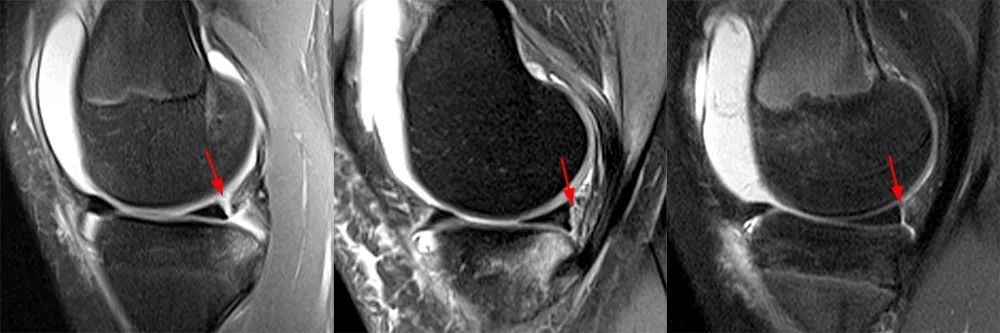

Hash等指出,Ramp损伤在MRI上的最突出 标志是在内侧半月板后角与后内侧关节囊之间插入了一个薄层的液体信号,观察内侧半月板后角与滑膜分离征象。

病例图片(均来自网络):